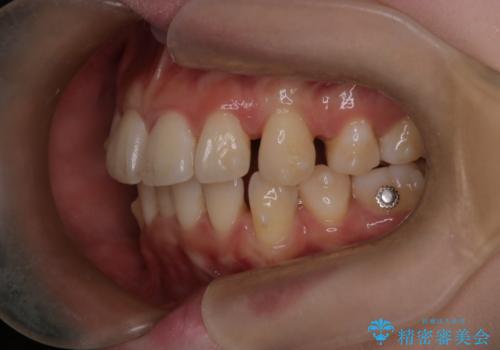

- 前歯が出ていることと、下の歯のがたがたで歯磨きがしにくいことを主訴に来院されました。

マウスピース矯正の希望があり、ワイヤーリカバリの可能性を伝えたうえでインビザライン抜歯矯正を行っています。

来院が途中途絶えたこともあり、4年ぐらい期間がかかりましたが、インビザラインだけで治療を終えることができました。